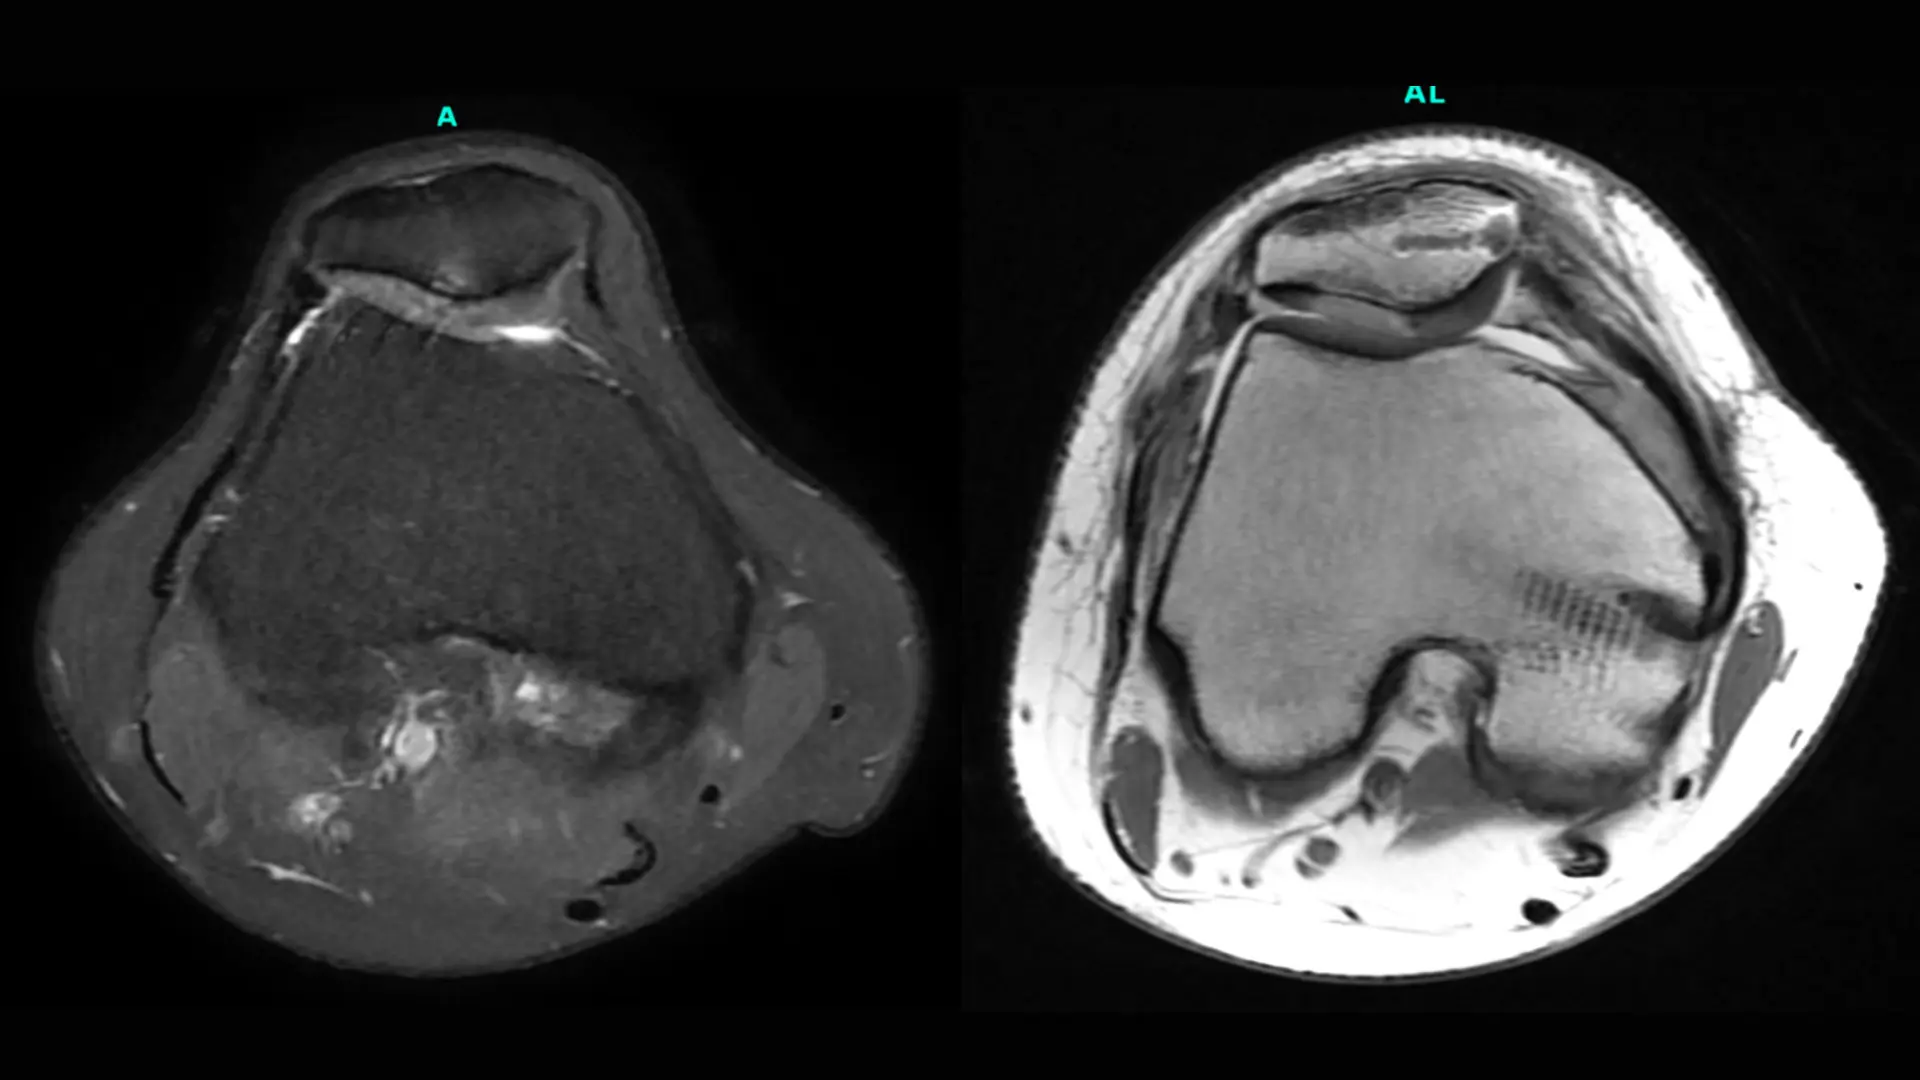

Image: A 31-year-old female patient presented with recurrent patellar instability and pain in the setting of a prior lateral release. An MRI demonstrated chondral breakdown of the lateral patellar facet. The patient underwent an MPFL reconstruction with anterior medializing tibial tubercle osteotomy and cell-based cartilage restoration to her patella.

Preoperative (left) and three-month postoperative (right) MRI axial images depicting incorporation of the patient’s cell-based cartilage graft as well as her MPFL reconstruction.